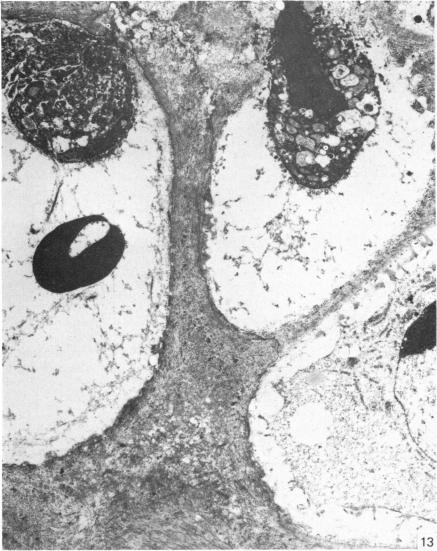

来自矮胖(stm)突变小鼠下颌髁突的异常软骨。

Abnormal cartilage from the mandibular condyle of stumpy (stm) mutant mice.

The mammalian mandibular condyle is composed of secondary cartilage and may thus be susceptible to genes causing achondroplasia and which result in abnormal++ primary cartilage formation. This paper describes the secondary cartilage in the mandible of the stumpy achondroplastic mutation in the mouse: both primary and secondary cartilage are affected by the gene.

哺乳动物的下颌髁由继发性软骨组成,因此可能易受导致软骨发育不全并致使初级软骨形成异常的基因影响。本文描述了小鼠短粗型软骨发育不全突变体下颌骨中的继发性软骨:初级软骨和继发性软骨均受该基因影响。